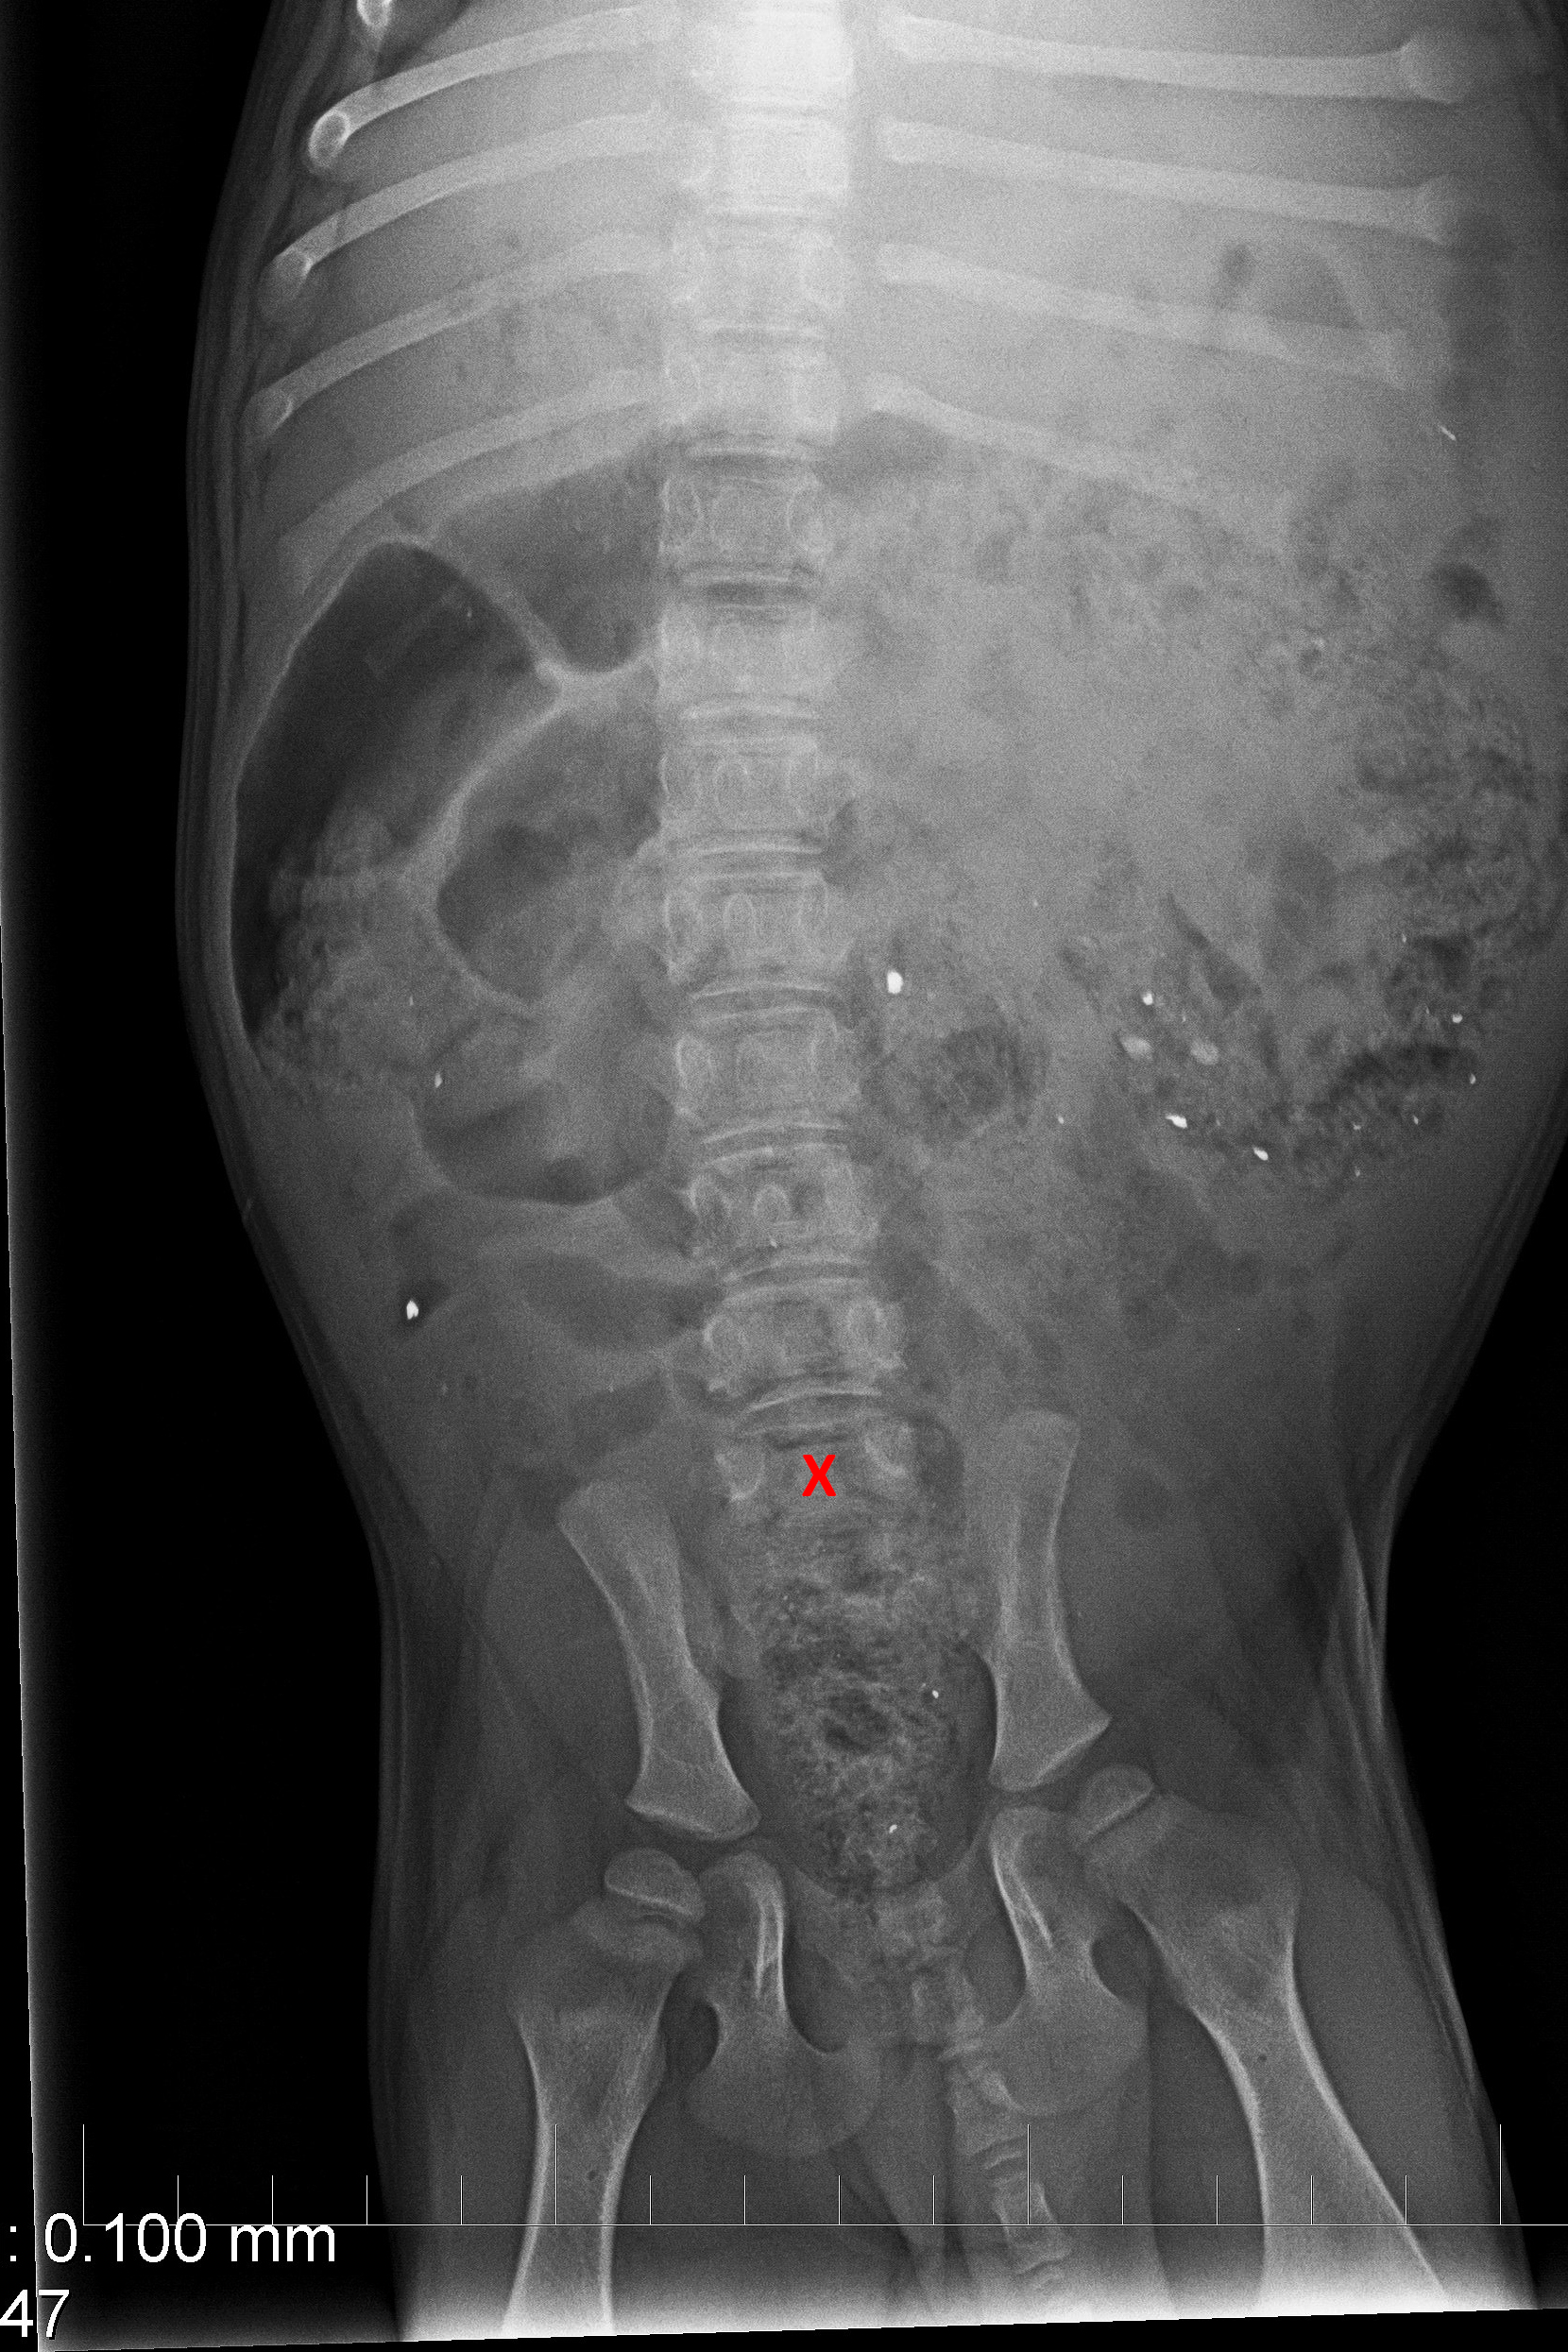

(2) 7 týdnů lat

(2) typ 3 I